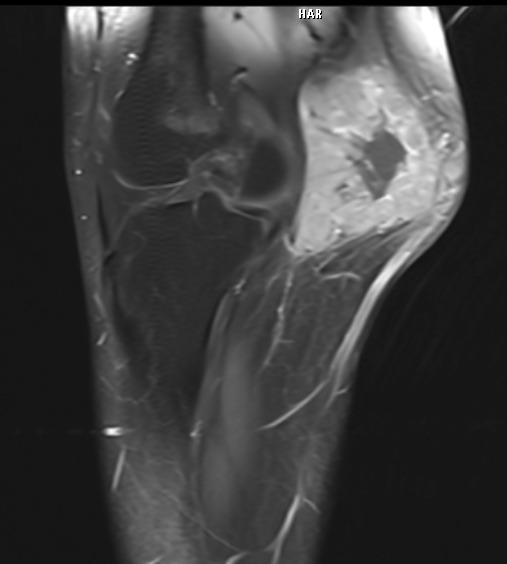

Muscle Cancer